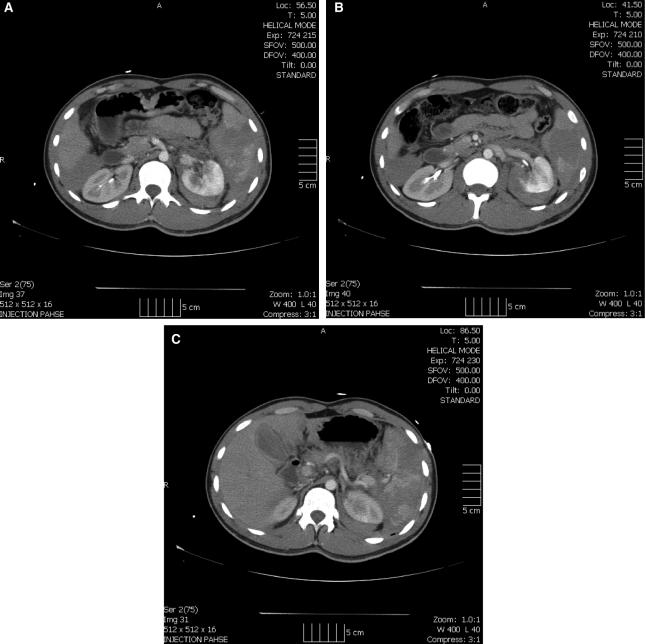

We describe the first reported use of laparoscopic splenectomy as initial treatment in high-grade blunt splenic trauma. A 21-year-old man sustained a blow to the left flank from a large construction pipe and was transferred to our hospital with a grade V splenic laceration and a grade II left peri-renal hematoma with hematuria. He was hemodynamically stable. He underwent a laparoscopic splenectomy shortly after arrival. The patient's renal injury was managed nonoperatively, and he was discharged home with no complications and has remained well.

我们报道了首例将腹腔镜脾切除术作为高级别钝性脾外伤初始治疗方法的应用。一名21岁男性被一根大型建筑管道击中左腹,被转送至我院,诊断为Ⅴ级脾裂伤和Ⅱ级左肾周血肿伴血尿。他血流动力学稳定。入院后不久,他接受了腹腔镜脾切除术。患者的肾损伤采用非手术治疗,出院时无并发症,恢复良好。